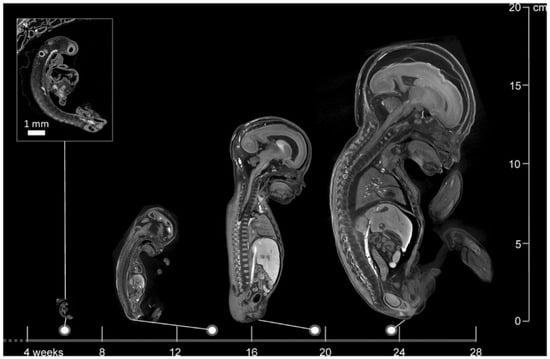

Figure 1.

Images of a 6-week-old embryo and 13-, 20-, and 24-week-old fetuses, created with micro-CT. This image illustrates the wide applicability in gestational age range of micro-CT. Scale bar represents 1 mm (Dawood et al. 2022 [62], with permission).

Using autopsy as a comparison, micro-CT appears to give promising results in identifying anatomical anomalies. A study involving 20 fetuses with gestational ages ranging from 11 to 21 weeks reported overall sensitivities of 93.8% and specificities of 100% for detecting congenital defects using micro-CT [69]. Another comprehensive study evaluating 268 micro-CT scans of fetuses between 11 and 24 weeks gestational age documented a sensitivity and specificity of 92.3% and 98%, respectively. These results imply that micro-CT serves as a good alternative to autopsy [70]. Moreover, maceration does not appear to affect micro-CT imaging quality, as high-resolution images were obtained in 95% of cases despite maceration [71]. Furthermore, micro-CT can operate on very small anatomical structures and provides increasing spatial resolution as fetal size decreases, making it a viable alternative where conventional autopsy is unfeasible (Figure 1) [62,70,72].

An overview was created of the cost, resolution, scanning time, and the ability to scan despite maceration for the three above-mentioned imaging techniques (Table 4). PMUS offers a relatively simple, accessible, and inexpensive way to scan fetuses. However, the resolution of the images is low and the technique is difficult to apply in miscarriages due to the small size and possible maceration of the fetus [77,79,80,82]. Both UHF-MRI and micro-CT produce relatively high-resolution images, but the resolution of micro-CT is significantly higher and the technique is less time-consuming and estimated to be more cost-effective than UHF-MRI [60,62,67,68,69,74,78,81] (Figure 2). As fetal size increases, micro-CT and UHF-MRI become less effective because of constraints such as the small bore size of UHF-MRI and the longer staining time required for micro-CT. Therefore, for fetuses beyond 20 weeks of gestation, low-field MRI is considered more appropriate (Figure 3) [67].